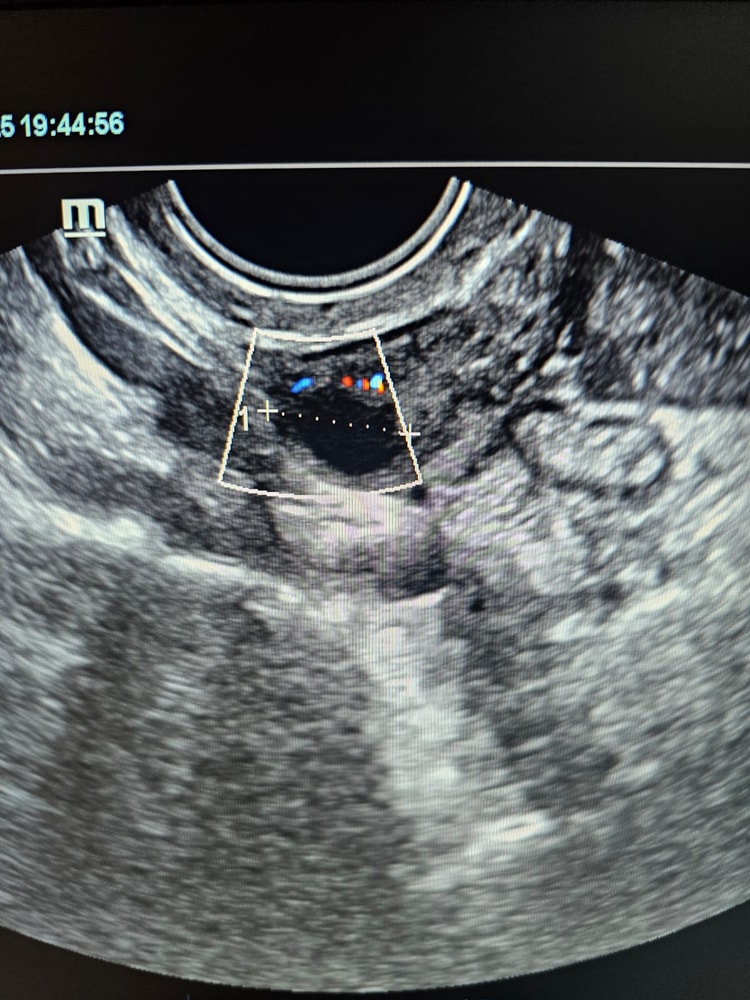

Хочу прикрепить фото и результаты первого узи и 2 которую проверили сего . У меня была истерика потому что в первый раз сказали что двойня но я надеюсь на лучшее и жду чудо. На 2 узи сказали что один плод , щас я не знаю как с этим смирится , и как понять один плод или 2. Но я до сих пор надеюсь что у меня там будут двоя